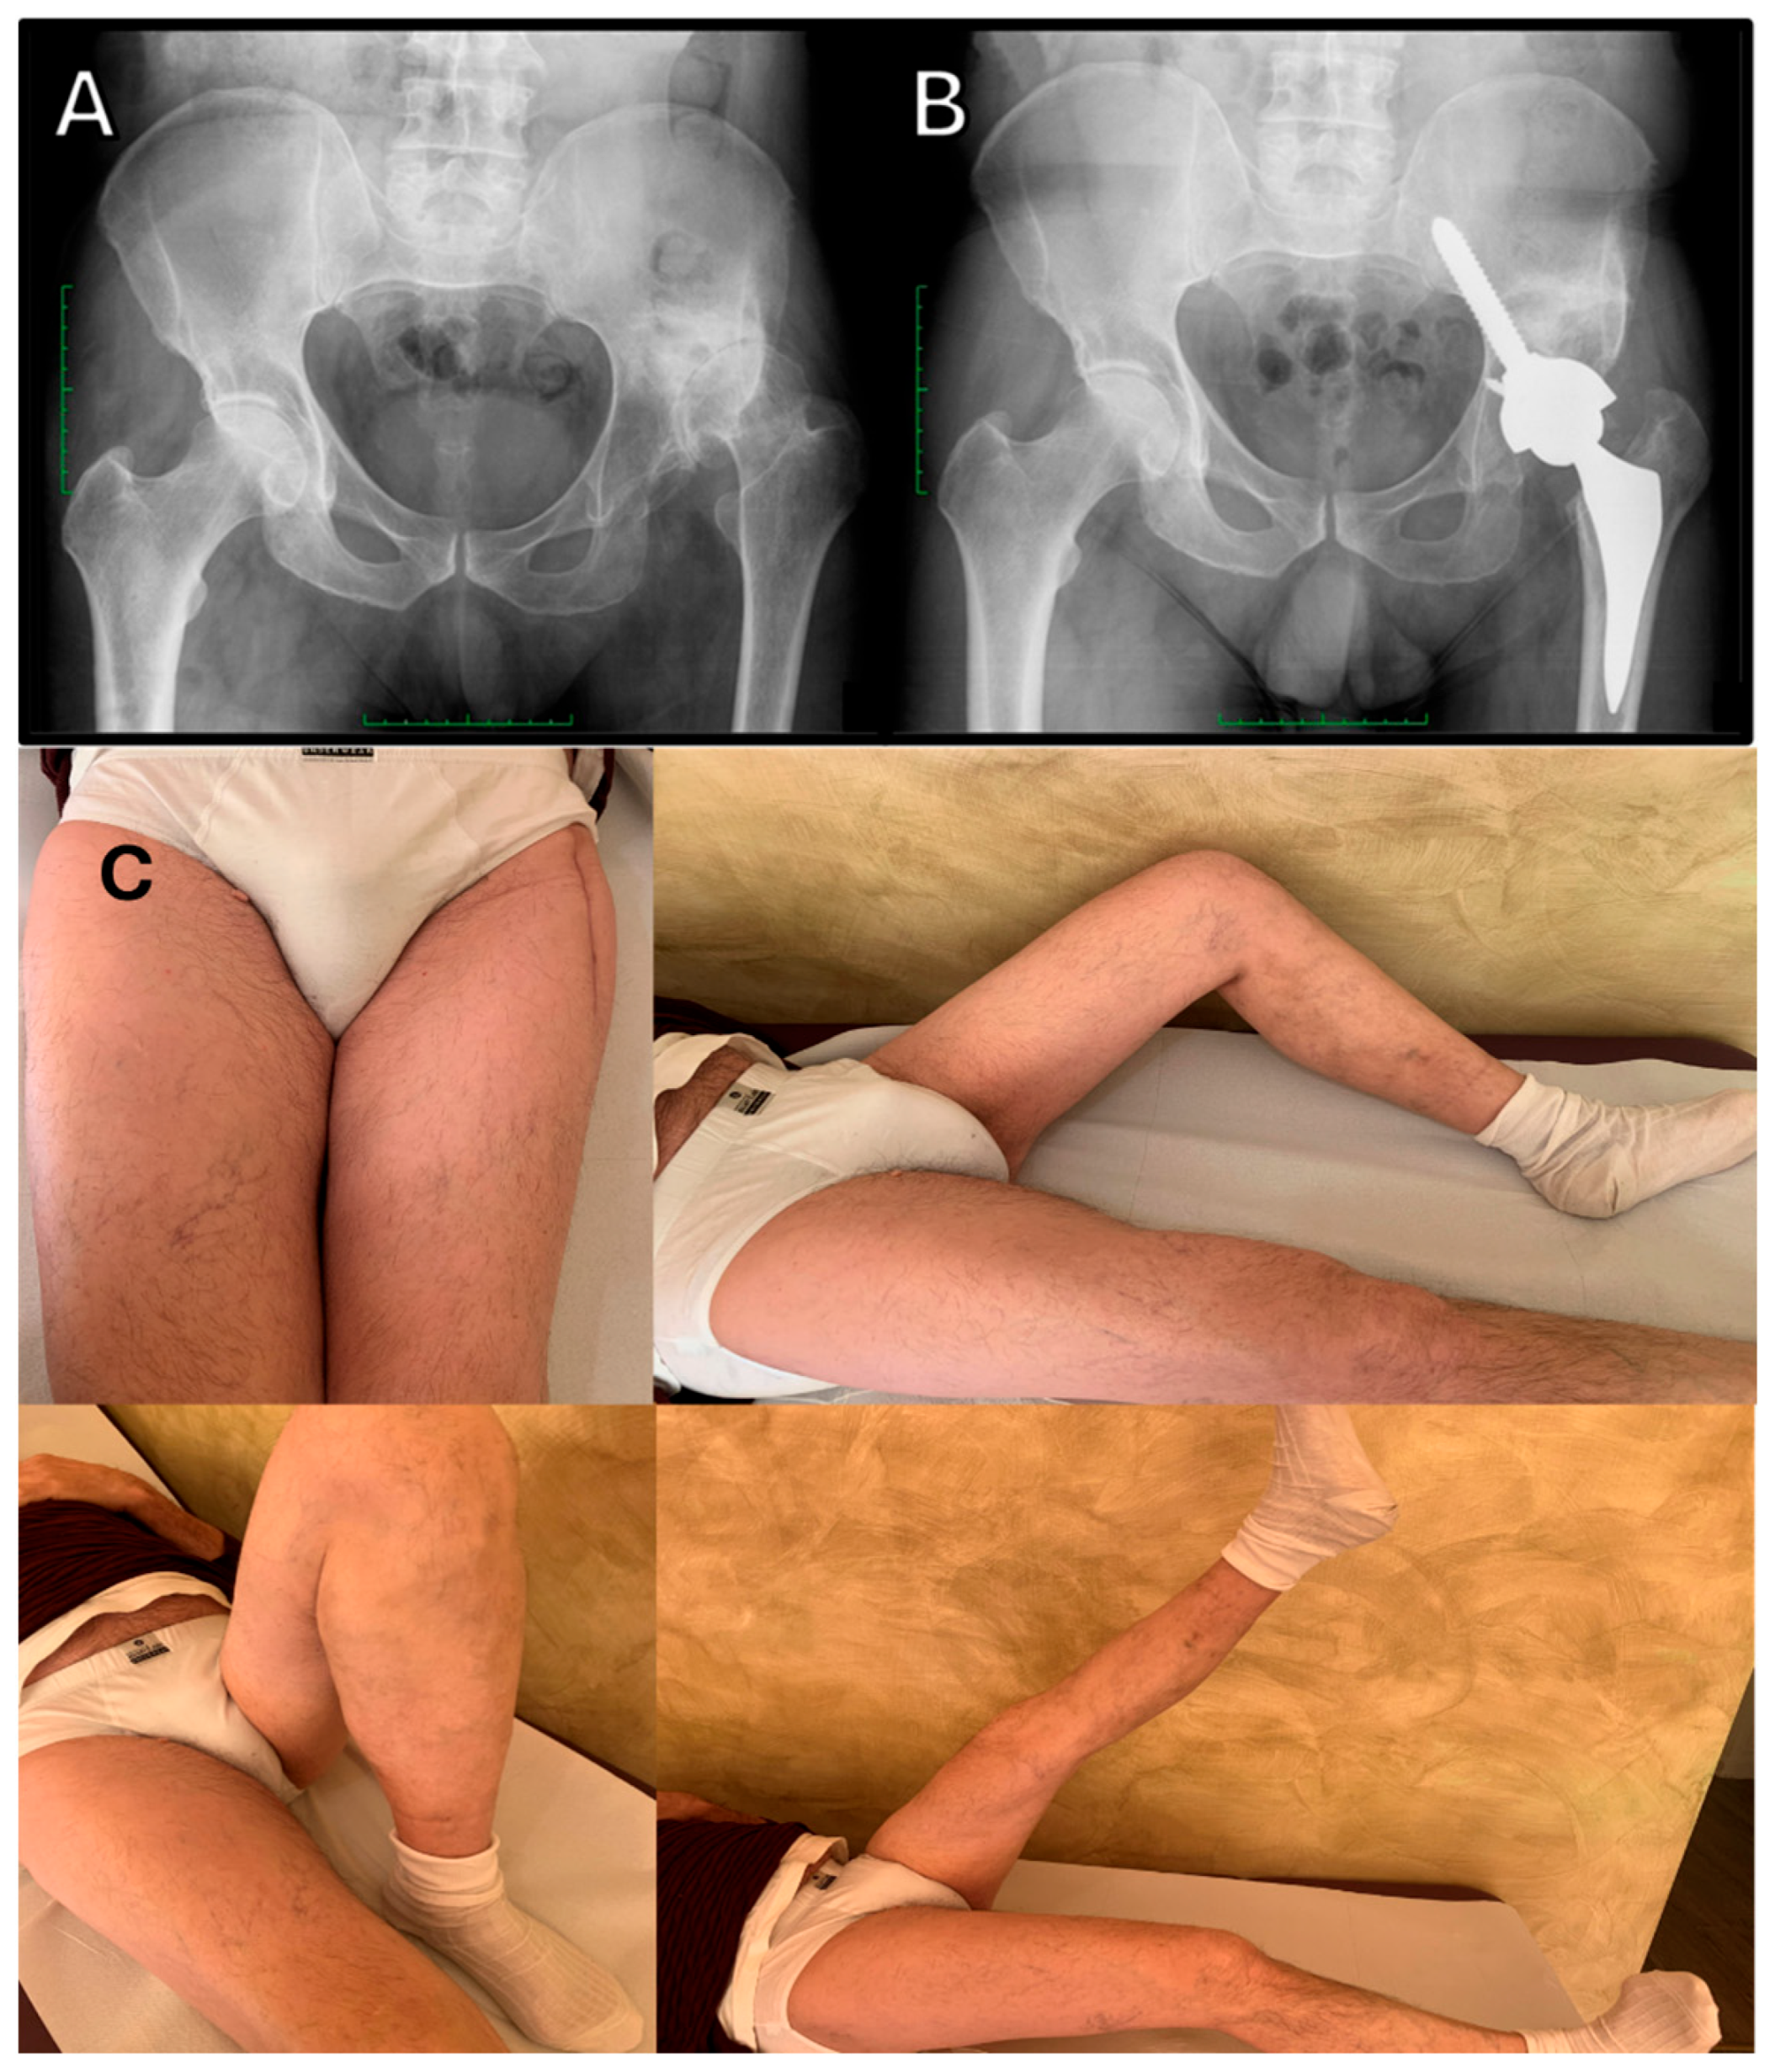

- Faldini, C.; Brunello, M.; Pilla, F.; Geraci, G.; Stefanini, N.; Tassinari, L.; Di Martino, A. Femoral Head Autograft to Manage Acetabular Bone Loss Defects in THA for Crowe III Hips by DAA: Retrospective Study and Surgical Technique. J. Clin. Med. 2023, 12, 751. [Google Scholar] [CrossRef]

- Faldini, C.; Tassinari, L.; Pederiva, D.; Rossomando, V.; Brunello, M.; Pilla, F.; Geraci, G.; Traina, F.; Di Martino, A. Direct Anterior Approach in Total Hip Arthroplasty for Severe Crowe IV Dysplasia: Retrospective Clinical and Radiological Study. Med. Kaunas. Lith. 2024, 60, 114. [Google Scholar] [CrossRef]